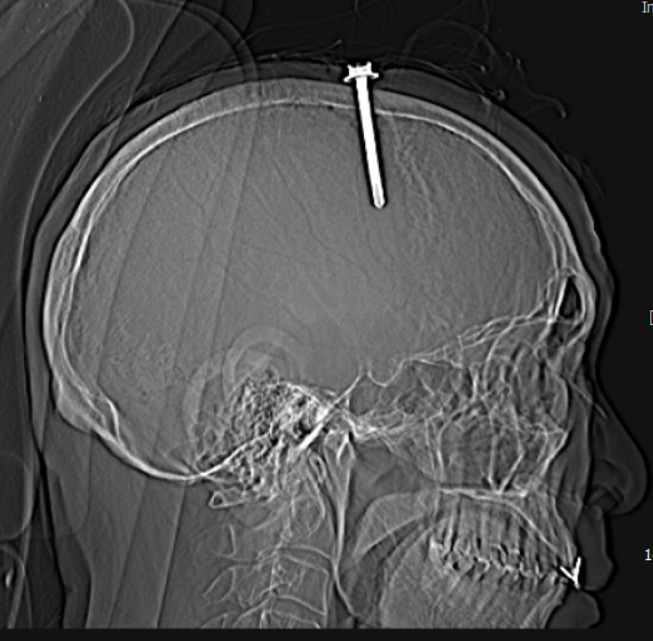

Qua thăm khám lâm sàng và kết quả chụp cắt lớp vi tính sọ não cho thấy bệnh nhân có vết thương sọ não, vết thương xoang tĩnh mạch dọc trên do dị vật kim loại cắm vào vùng đỉnh bên trái, cạnh xoang tĩnh mạch dọc trên. Dị vật có đường kính 0.5 cm, chiều dài 5,1cm.

![]() |

| Hình ảnh cây đinh trên phim chụp cắt lớp sọ não - Ảnh BVCC |